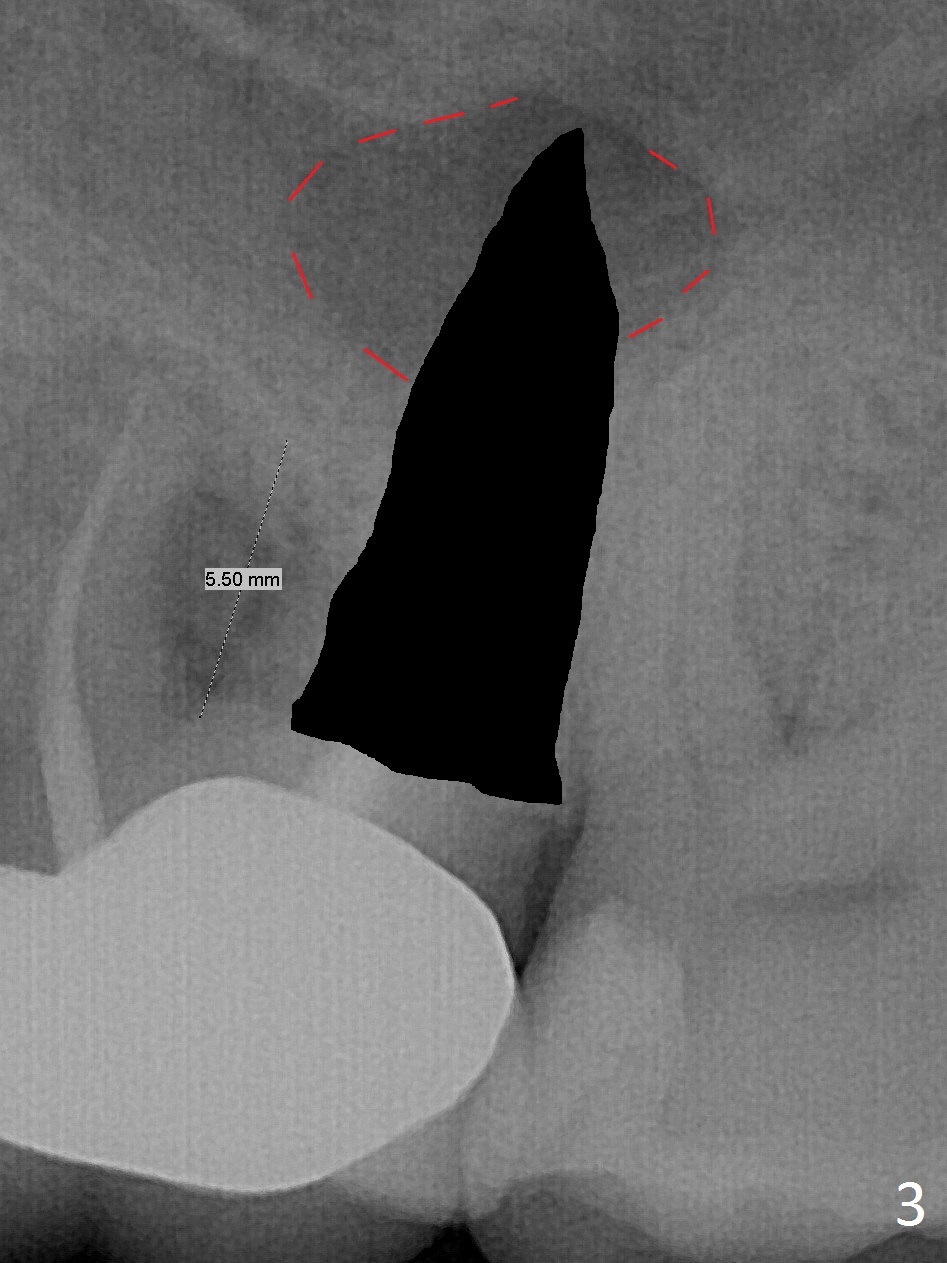

What is unclear preop is the large periapical radiolucency (Fig.1 red dashed line) of the palatal root (P) of the tooth #14. When the tooth is extracted, it is difficult to remove granulation tissue from the palatal apical socket, which is enlarged (Fig.2 (impression of sockets),3). The small dimension of the septum (~4x5 mm (Fig.1 pink) is also unrecognized preop, which leads to sinus perforation when 4.8 mm Magic Drill is used. In spite of use of PRF plug and membrane, allograft does not stay in the osteotomy after placement of 4x11 mm dummy implant or 5 mm tap drill (Fig.4 for 9 mm). Finally a 5.5x7 mm IBS implant is placed with 30 Ncm (Fig.5). After placement of Osteogen plug in the apical portion of the sockets, allograft/Osteogen is placed in the remaining sockets (Fig. 5 *). The latter is partially contained by a 6.5x4(3) mm abutment (A) and ultimately by an immediate provisional.

To avoid sinus membrane perforation, the initial osteotomy should be coronal to the sinus floor by 1 mm.